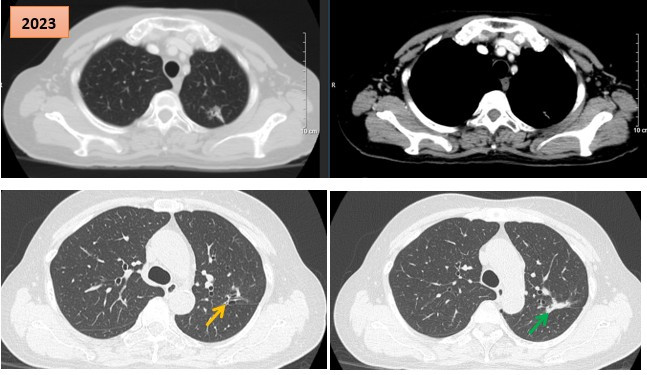

Hình ảnh cắt lớp vi tính theo dõi trong quá trình điều trị, tổn thương xơ hóa tại vị trí u cũ (mũi tên xanh) và giãn khu trú các nhánh phế quản liền kề (mũi tên vàng).

Kết quả chụp cắt lớp vi tính (CT) lồng ngực cho thấy khối u thùy trên phổi trái kích thước 20x15mm, bờ tua gai, xâm lấn rãnh liên thùy, kèm theo nhiều nốt mờ rải rác hai phổi, kích thước 5-10mm, phù hợp với tổn thương thứ phát, cùng hạch rốn phổi trái kích thước 10mm.

Sau 6 tháng điều trị, triệu chứng đau ngực giảm rõ rệt, bệnh nhân dung nạp thuốc tốt. Tác dụng phụ chủ yếu là ban da dạng chấm và mụn ở vùng đầu, vùng sinh dục – những biểu hiện thường gặp của thuốc và được đánh giá là dấu hiệu dự báo đáp ứng điều trị tốt. Kết quả chụp CT kiểm tra cho thấy khối u đáp ứng điều trị, chuyển thành tổn thương xơ hóa, giảm ngấm thuốc sau tiêm.

Bệnh nhân tiếp tục được theo dõi và điều trị duy trì bằng erlotinib. Đến thời điểm đánh giá lại vào tháng 5/2023, sau 6 năm điều trị liên tục, bệnh nhân vẫn trong tình trạng ổn định: Không đau ngực, không khó thở, các chỉ điểm khối u CEA và Cyfra 21-1 duy trì trong giới hạn bình thường.

Kết quả chụp CT ngực-bụng và cộng hưởng từ sọ não không ghi nhận thêm tổn thương mới. Tại vị trí u cũ, tổn thương xơ hóa gây co kéo rãnh liên thùy và giãn khu trú các nhánh phế quản lân cận, song không ảnh hưởng đến chức năng hô hấp và không gây triệu chứng lâm sàng.